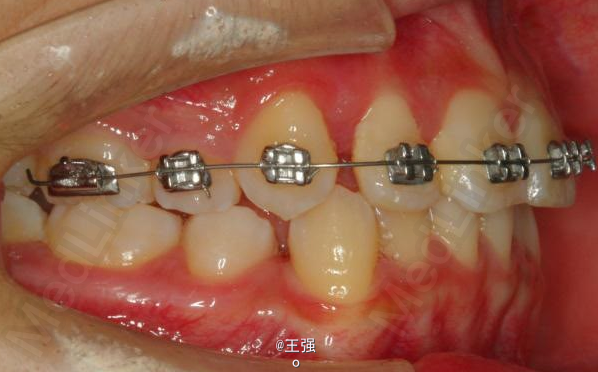

在临床上,我们常常会遇到亚类病例,对于亚类病例,有时需要不对称拔牙,常见的不对称拔牙方法有:上颌对称,下颌数目对称但是位置不对称。还有上颌对称,但是下颌数目不对称。其目的就是为了取得尽可能理想的尖窝对应咬合关系 该病例右侧是中性关系,左侧是中性偏远中关系,上颌中线正,下颌中线左偏约1mm。左侧磨牙关系距离中性关系约差2mm左右。如果采用对称性拔除下颌左右四,我们面临的问题是,一、如何保证矫治后上下中线一致,二、如何保证左侧磨牙关系矫治后为中性关系。治疗过程中势必会用到不对称牵引。我个人认为除非是功能性的因素,矫治过程中最好不要用不对称牵引。 关于中线和磨牙关系的问题,我认为应在矫治计划制定时就应考虑到,而不是等到矫治第三阶段所谓精细调整阶段再来解决。事实上到了这个阶段采用了不对称的牵引,即使暂时取得了中线对齐的矫治目的也是不稳定的。 这个病例,用了不对称的拔牙,右下拔四,左下拔五。下颌牙齿在漂移的过程中(几乎没有外来力量),下前牙自然就会向右比向左多漂移一些,中线在下颌还没有开始矫治时就对齐了,左下六因没有五的存在,自然就向近中多漂移一些,和上颌六形成中性关系。接下来的矫治就会非常简单,而结果自然也非常稳定。